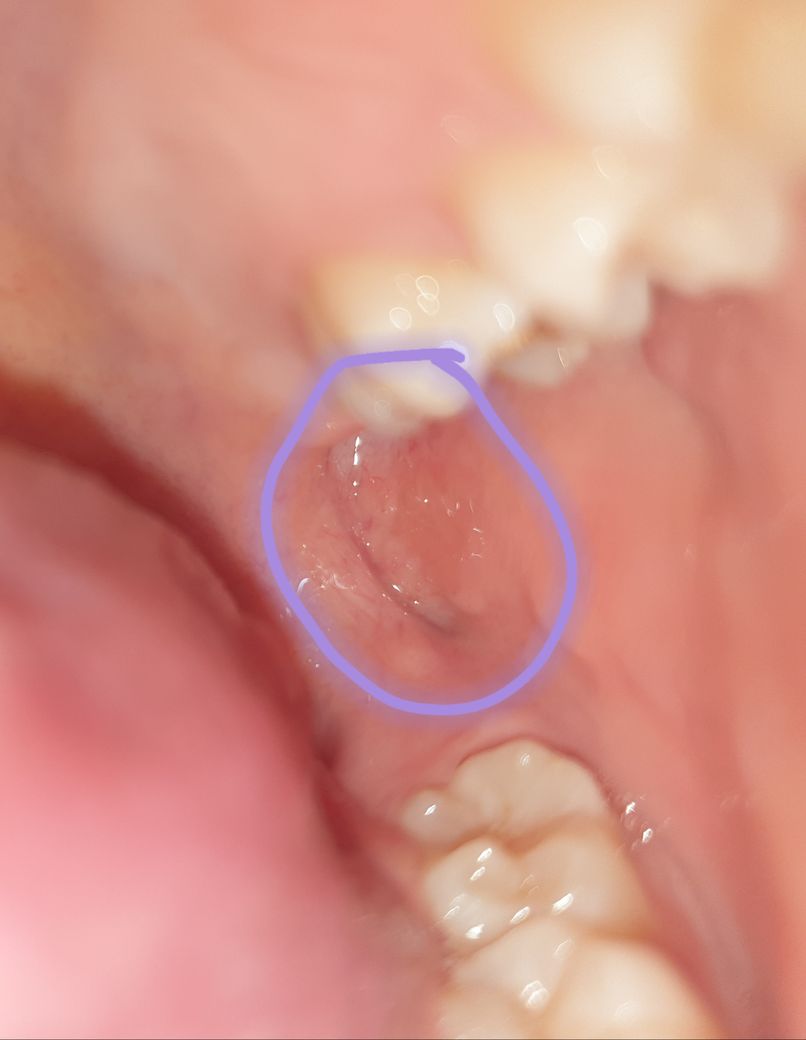

안녕하세요. 며칠 전부터 입 내부에 뭐가 생겼는데 닿으면 아프네요 깨문 기억도 없고 깨물 수도 없는 부위 같은데 왜 생긴 걸까요 ㅜㅜ 단순한 외상인지 다른 질병인지 궁금합니다!

현재 사진으로 보아서는 구내염일 가능성이 매우 높아 보입니다. 구내염은 여러가지 원인에 의해 나타나게 되며 교합이상, 외상, 음식물에 의한 자극 ,마찰 등에 의해서도 나타날 수 있습니다. 단순 구내염이라면 2주 이내에 회복되는 성질이 있으나 2주가 지났는데도 증상이 호전되지 않는다면 치과 방문 후 감별진단을 받아보셔야 합니다.

환자분의 치아가 그쪽을 씹으신거 같아요. 크게 문제가 잇는건 아니고 시간이 지나면괜찮아 지실꺼에요. 최대한 그쪽에 자극이 가지 않도록만 해주세요.